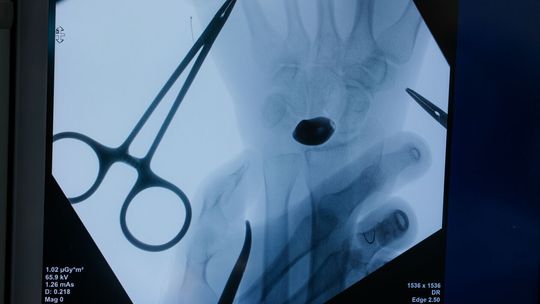

Przygotowania do operacji trwały rok. Lekarze wykonali cyfrowy model nadgarstka, na podstawie którego powstał implant z biokompatybilnego stopu tytanu. Powierzchnie odpowiedzialne za ruch i kontakt ze stawem wygładzono lub pokryto powłoką diamentopodobną, aby zminimalizować tarcie.

Zabieg przeprowadził zespół pod kierownictwem dr. n. med. Piotra Piecha.